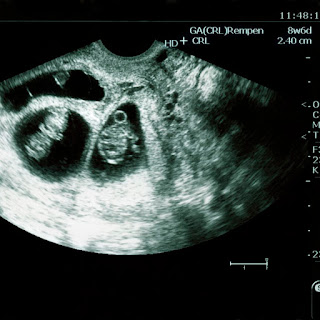

Confirm The Number of Babies

You can also confirm the number of babies you are

going to have. If it's multiple pregnancies, then preparing for them beforehand

is essential.

Confirm The Gestational Age

Secondly, you need to determine your baby's

gestational age. Once you determine the age, you can know the date you became

pregnant. This will help you know the approximate date your baby will be born.